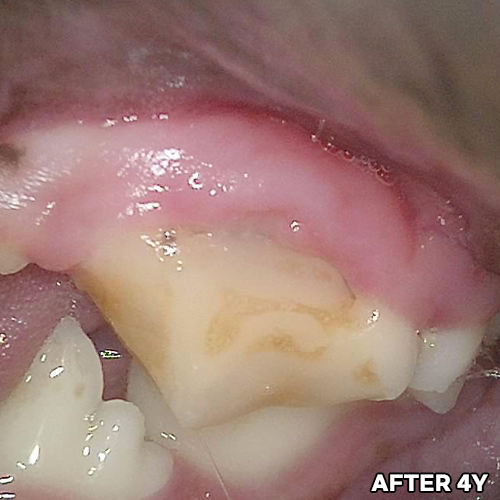

최고 난이도 강아지신경치료 - 꽉막힌 근관&치수괴사! 커다란 반려견치근단농양! 녹아내린 턱뼈! 치통으로 사나워진 모습! 강아지 신경치료 & 치주치료 한달 뒤 좋아졌어요!